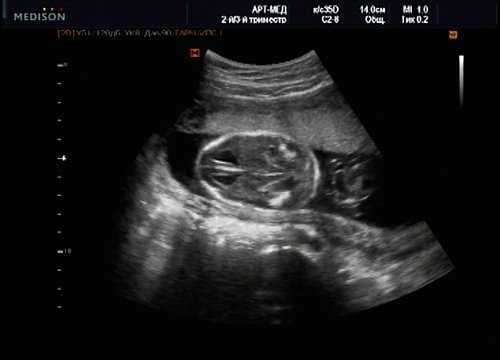

В равной степени это относится к дефекту межжелудочковой перегородки (рис. 6), простой форме транспозиции магистральных сосудов (рис. 7, 8), транспозиции магистральных сосудов с дефектом межжелудочковой перегородки (синдром Тауссиг - Бинга) (рис. 9), общему желудочку (рис. 10), общему артериальному стволу (рис. 10), двойному отхождению сосудов от одного из желудочков сердца (рис. 11).

Рис. 6. Дефект межжелудочковой перегородки. Длинная ось сердца. Стрелками показан дефект межжелудочковой перегородки.